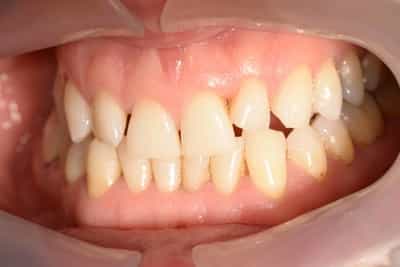

Situation Initiale

Etude du cas et proposition